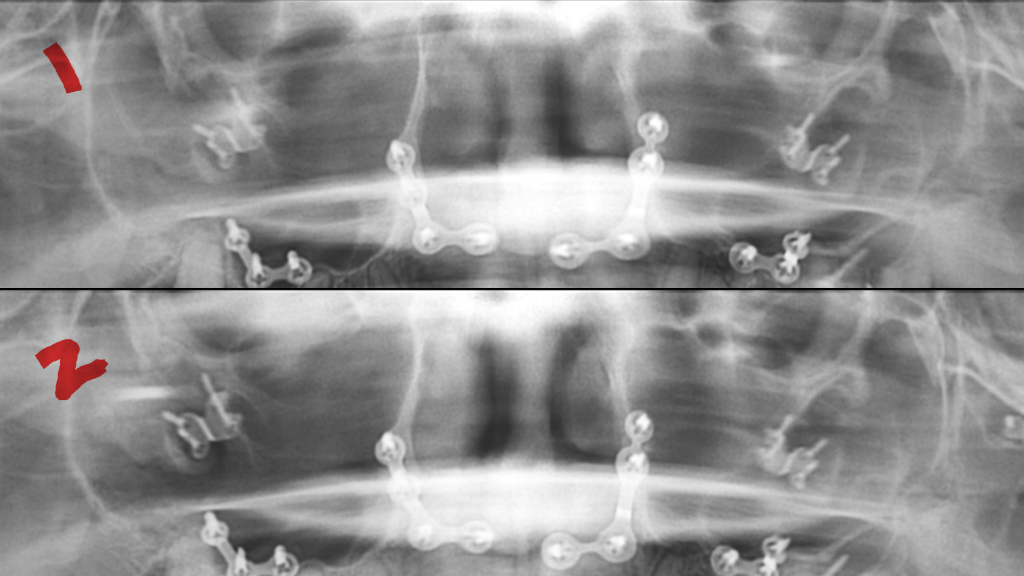

첫번째 사진은 3개월전 입니다.

• 1번 째 사진

상악동에 염증이 있다면 상악동의 벽면을 따라서 방사선상 불투과성이 보이는 경우가 많습니다 .

파노라마 상에는 큰이상이 없어 보이기는 하지만 여러 구조물이 겹쳐서 나오기 때문에 상악동여부를 확인하기는 정확하지는 않으며 CT사진을 본다면 더 정확하게 확인을 할수 있습니다.

턱교정 수술로 양악수술 하신 것으로 보입니다. 양쪽 상악동 부위가 검은색으로 보이기 때문에 이는 정상적인 상악동 소견입니다. 만약 상악동염이 있다면 검게 안보이고 약간 뿌옇게 보입니다.

양악수술을 하신게 아닌가요? 수술때문에 그럴가능성이 있는거 같습니다. 사진상에서는 크게 상악동염이 많아 보이진 않습니다.

다만, 2개의 방사선 사진으로 봐서는 특별한 문제점은 발견되지 않습니다.

코막힘, 악취, 머리 띵한 증상 등이 동반된다면 부비동염의 가능성도 있으나 마찬가지로 방사선 사진상에서 관찰되지는 않습니다.